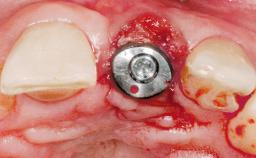

Immediate Flapless Placement of an Implant in a Maxillary Left Central Incisor Site

A 42-year-old female patient was referred to our clinic at the School of Dentistry of the University of São Paulo in November 2004, presenting a deficient restoration in the upper left central incisor. The clinical examination revealed no gingival retraction or any signs of gingival inflammation and, therefore, previous periodontal treatment was not considered. The patient presented a high lip line at full smile and a thin tissue biotype. This combination characterized a high-risk situation from an anatomic point of view, which required careful preoperative planning and cautious surgical execution.

Placement Protocol Immediate implant placement

Tooth Site Maxillary incisor or canine

Loading Protocol Immediate

Provisional Implant-Supported Prosthesis Prosthodontic margin < 3 mm apical to mucosal margin Prosthodontic margin < 3 mm apical to mucosal margin